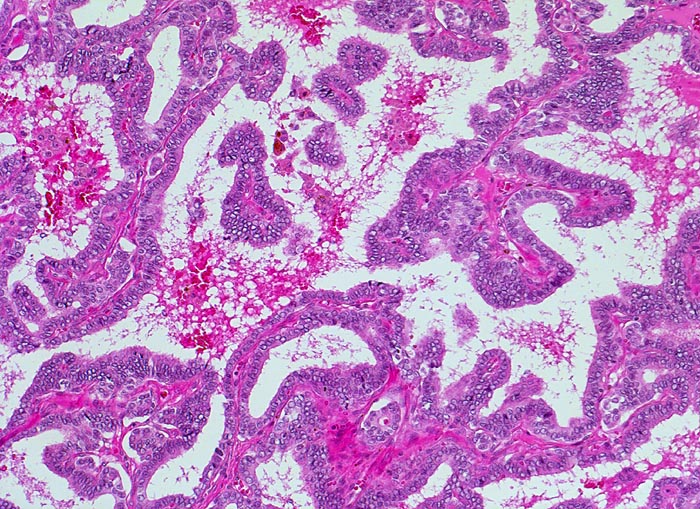

Histologisch finden sich bei der klassischen Variante des papillären Schilddrüsenkarzinoms verzweigte Papillen mit einem zentralen fibrovaskulären Stiel und/oder Follikel, welche von Zellen mit den morphologischen Charakteristika eines papillären Karzinoms ausgekleidet sind. In der Hälfte der Fälle können Verkalkungen in Form von Psammomkörperchen nachgewiesen werden. Bei der follikulären Variante des papillären Karzinoms bilden die Tumorzellen Follikel. Die neoplastischen Follikel sind von Zellen mit der typischen Morphologie des papillären Karzinoms (gekerbte Kerne mit aufgelockertem Chromatin und intranukleäre Vakuolen (> 5425)) ausgekleidet. Daneben existieren verschiedene weitere histologische Subtypen des papillären Karzinoms: kolumnarzellige Variante (columnar cell), großzellige Variante (tall cell), diffuse sklerosierende Variante, onkozytäre Variante, und solide Variante. Kombinationen dieser Subtypen kommen vor. Die diffuse sklerosierende Variante (2% der Fälle), welche bei jüngeren Patienten auftritt, kann eine Struma ohne palpable Knoten ausbilden und klinisch mit einer Autoimmunthyreoiditis verwechselt werden.

• Der Tumor besteht aus Papillen mit einem fibrovaskulären Stromastiel und neoplastischen Follikeln.

• Dicht gelagerte, einander überlappende Tumorzellen mit der typischen Zytomorphologie des papillären Karzinoms:

• Vergrösserte Zellkerne (im Vergleich zu den Zellkernen der nicht neoplastischen Follikelepithelien)

• Zellkerne mit zentraler Aufhellung des Chromatins (Milchglaskerne).

• Kernkerben (Grooves).

• Eindellungen der Kernmembran.

• Kleiner Nukleolus.